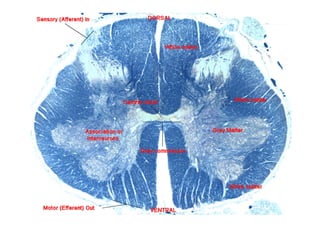

Septo dorsal medial

Funículo dorsal

da substância branca

Funículo lateral

Funículo ventral

Coluna dorsal

(posterior)

Coluna intermediária

Coluna ventral

(anterior)

SUBSTÂNCIA

BRANCA

CINZENTA

Fissura mediana anterior

Substância cinzenta

intermédia central

Cross-section through the spinal cord at the mid-thoracic level.